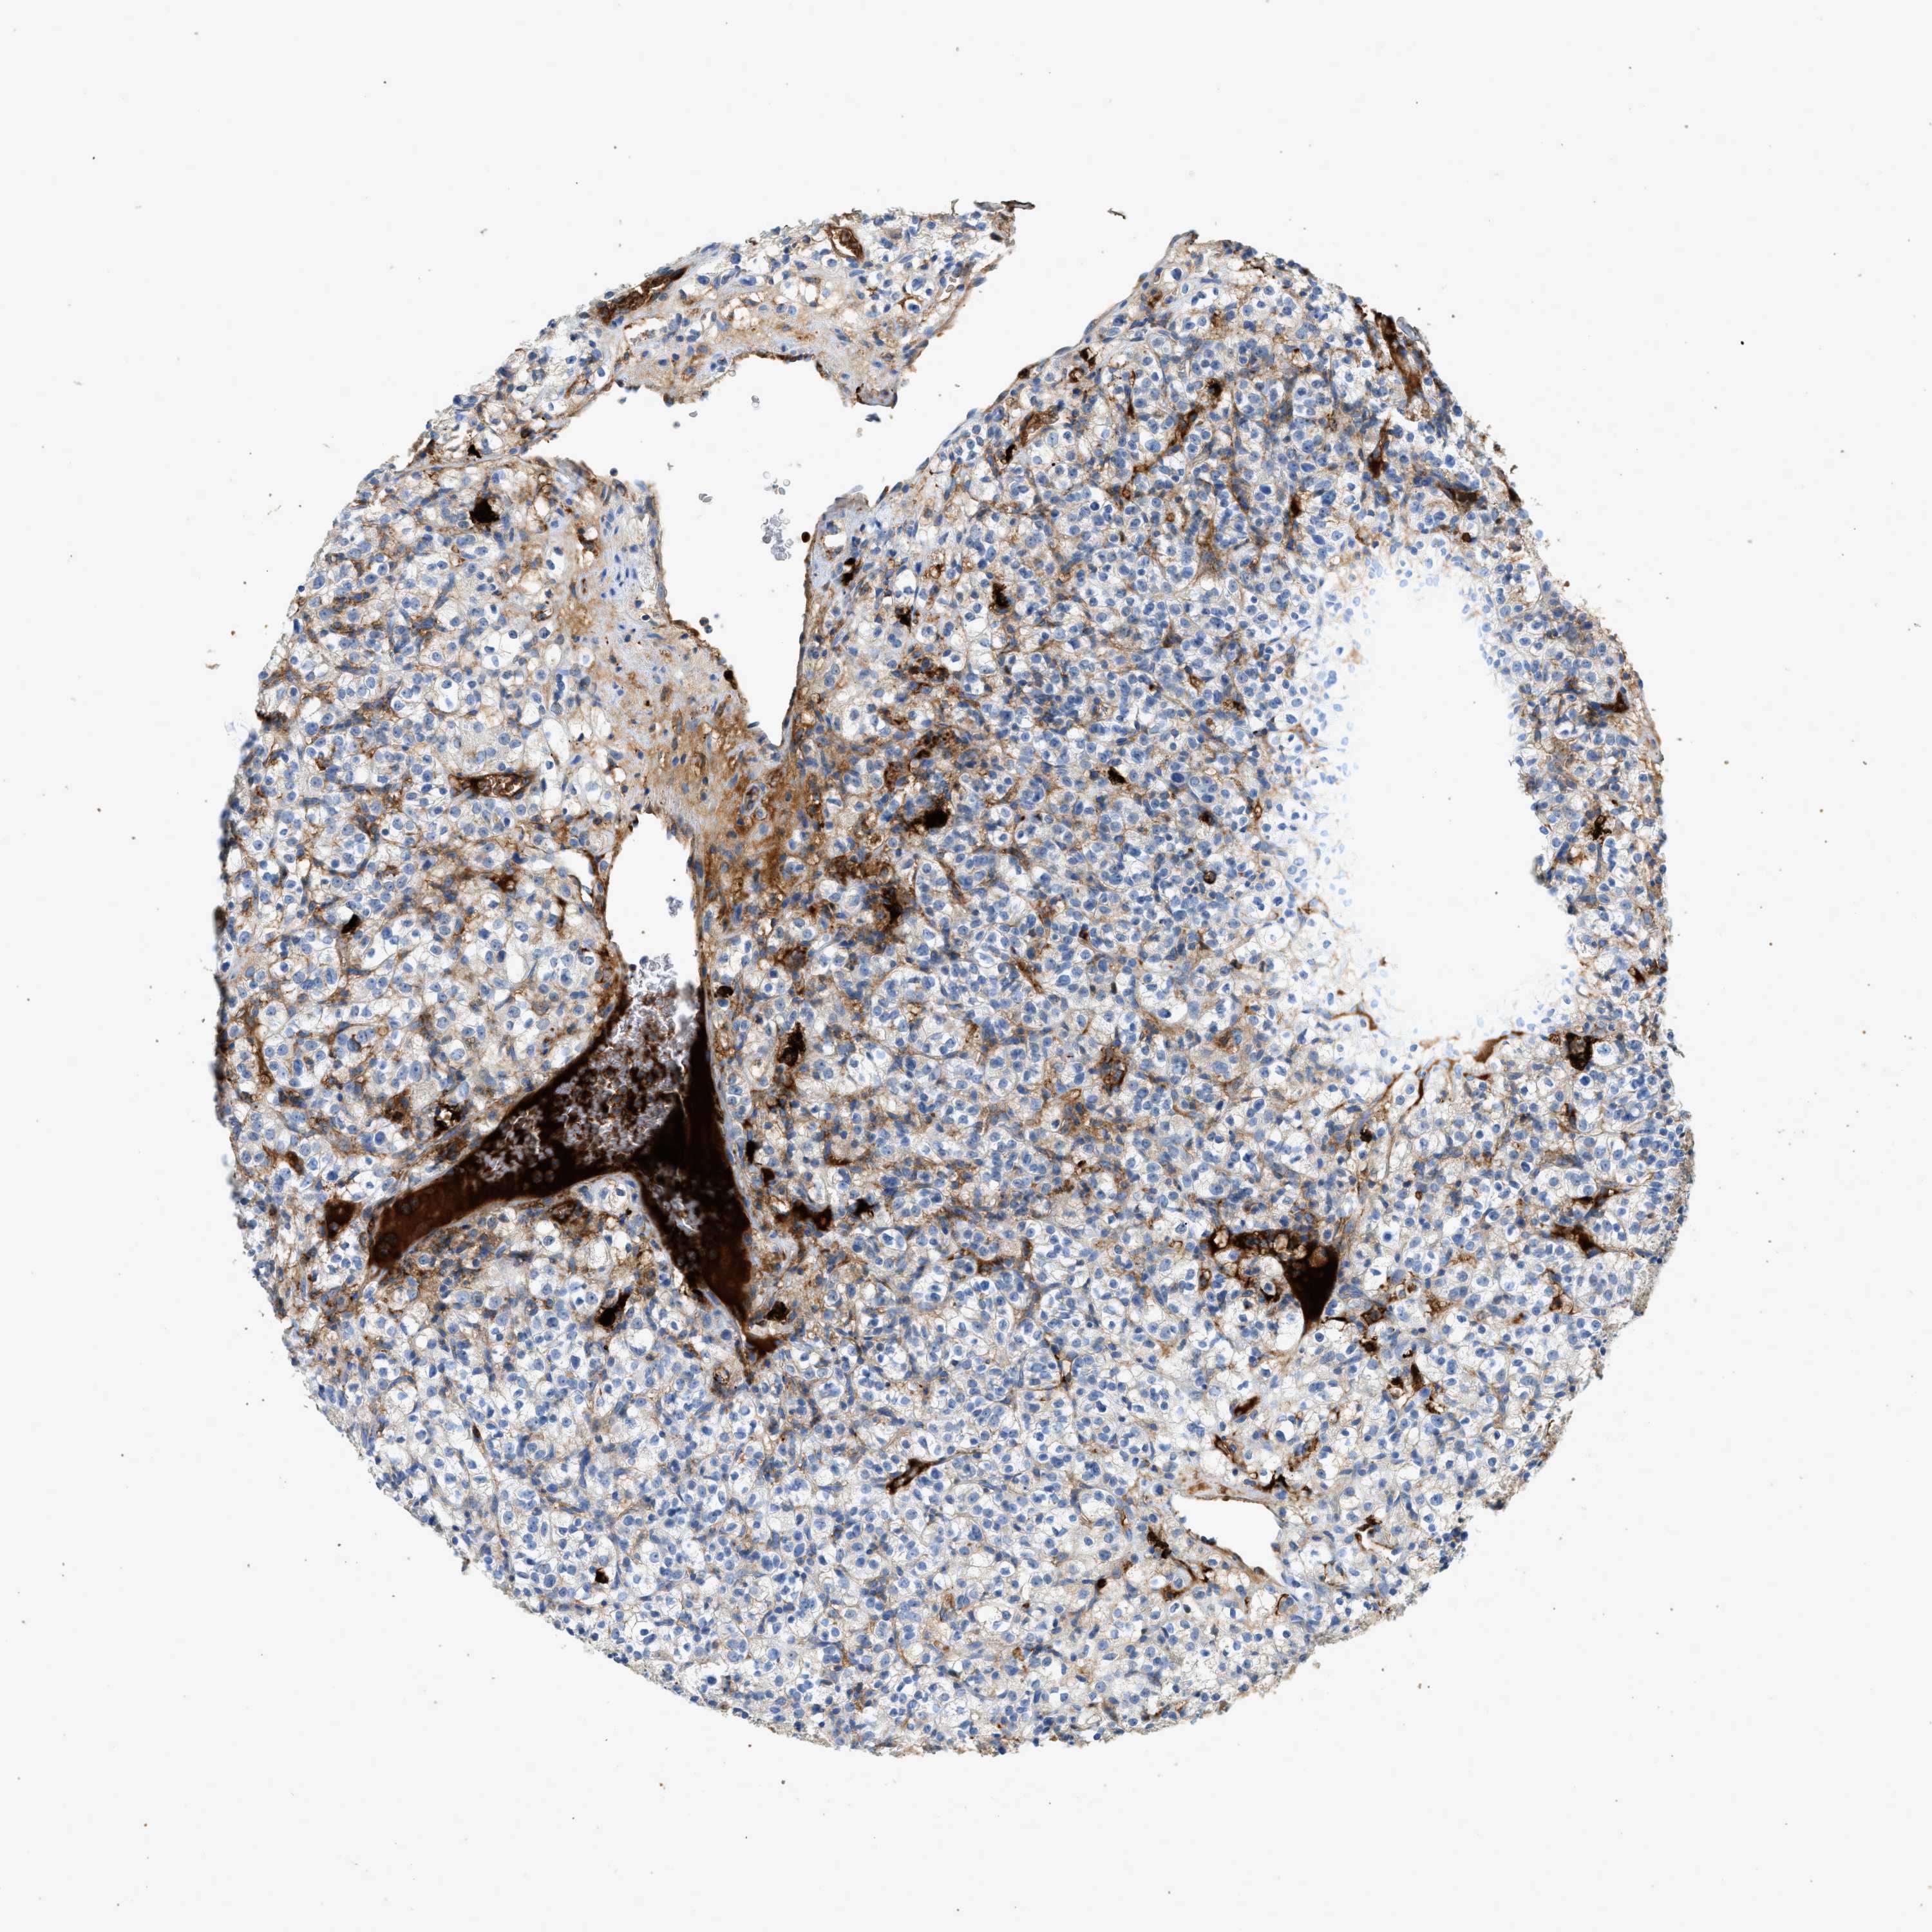

CANCER RENAL CANCER Show tissue menu

KICH TCGA KIRC TCGA KIRC VALIDATION KIRP TCGA PROTEIN RCC CPTAC PROTEIN EXPRESSION